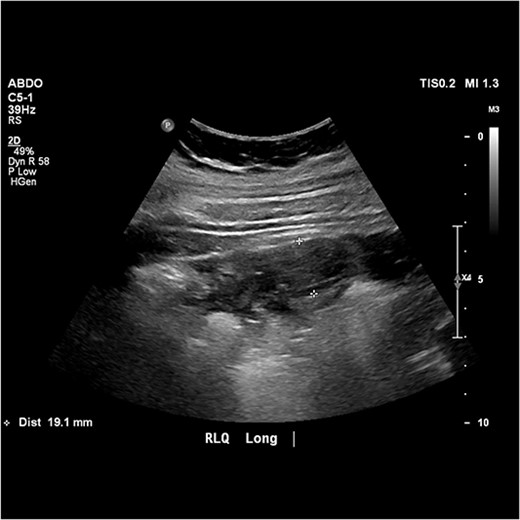

Urgent pelvic ultrasound was performed which described a 19 mm blind ending tubular structure with surrounding hyperaemia, echogenic fat and focal tenderness, which was marked by the sonographer in the right upper quadrant and deemed compatible with acute appendicitis (Fig. 1).

Image from abdominal ultrasound demonstrating hyperaemic, tubular structure measuring 19.1 mm in width with echogenic fat.